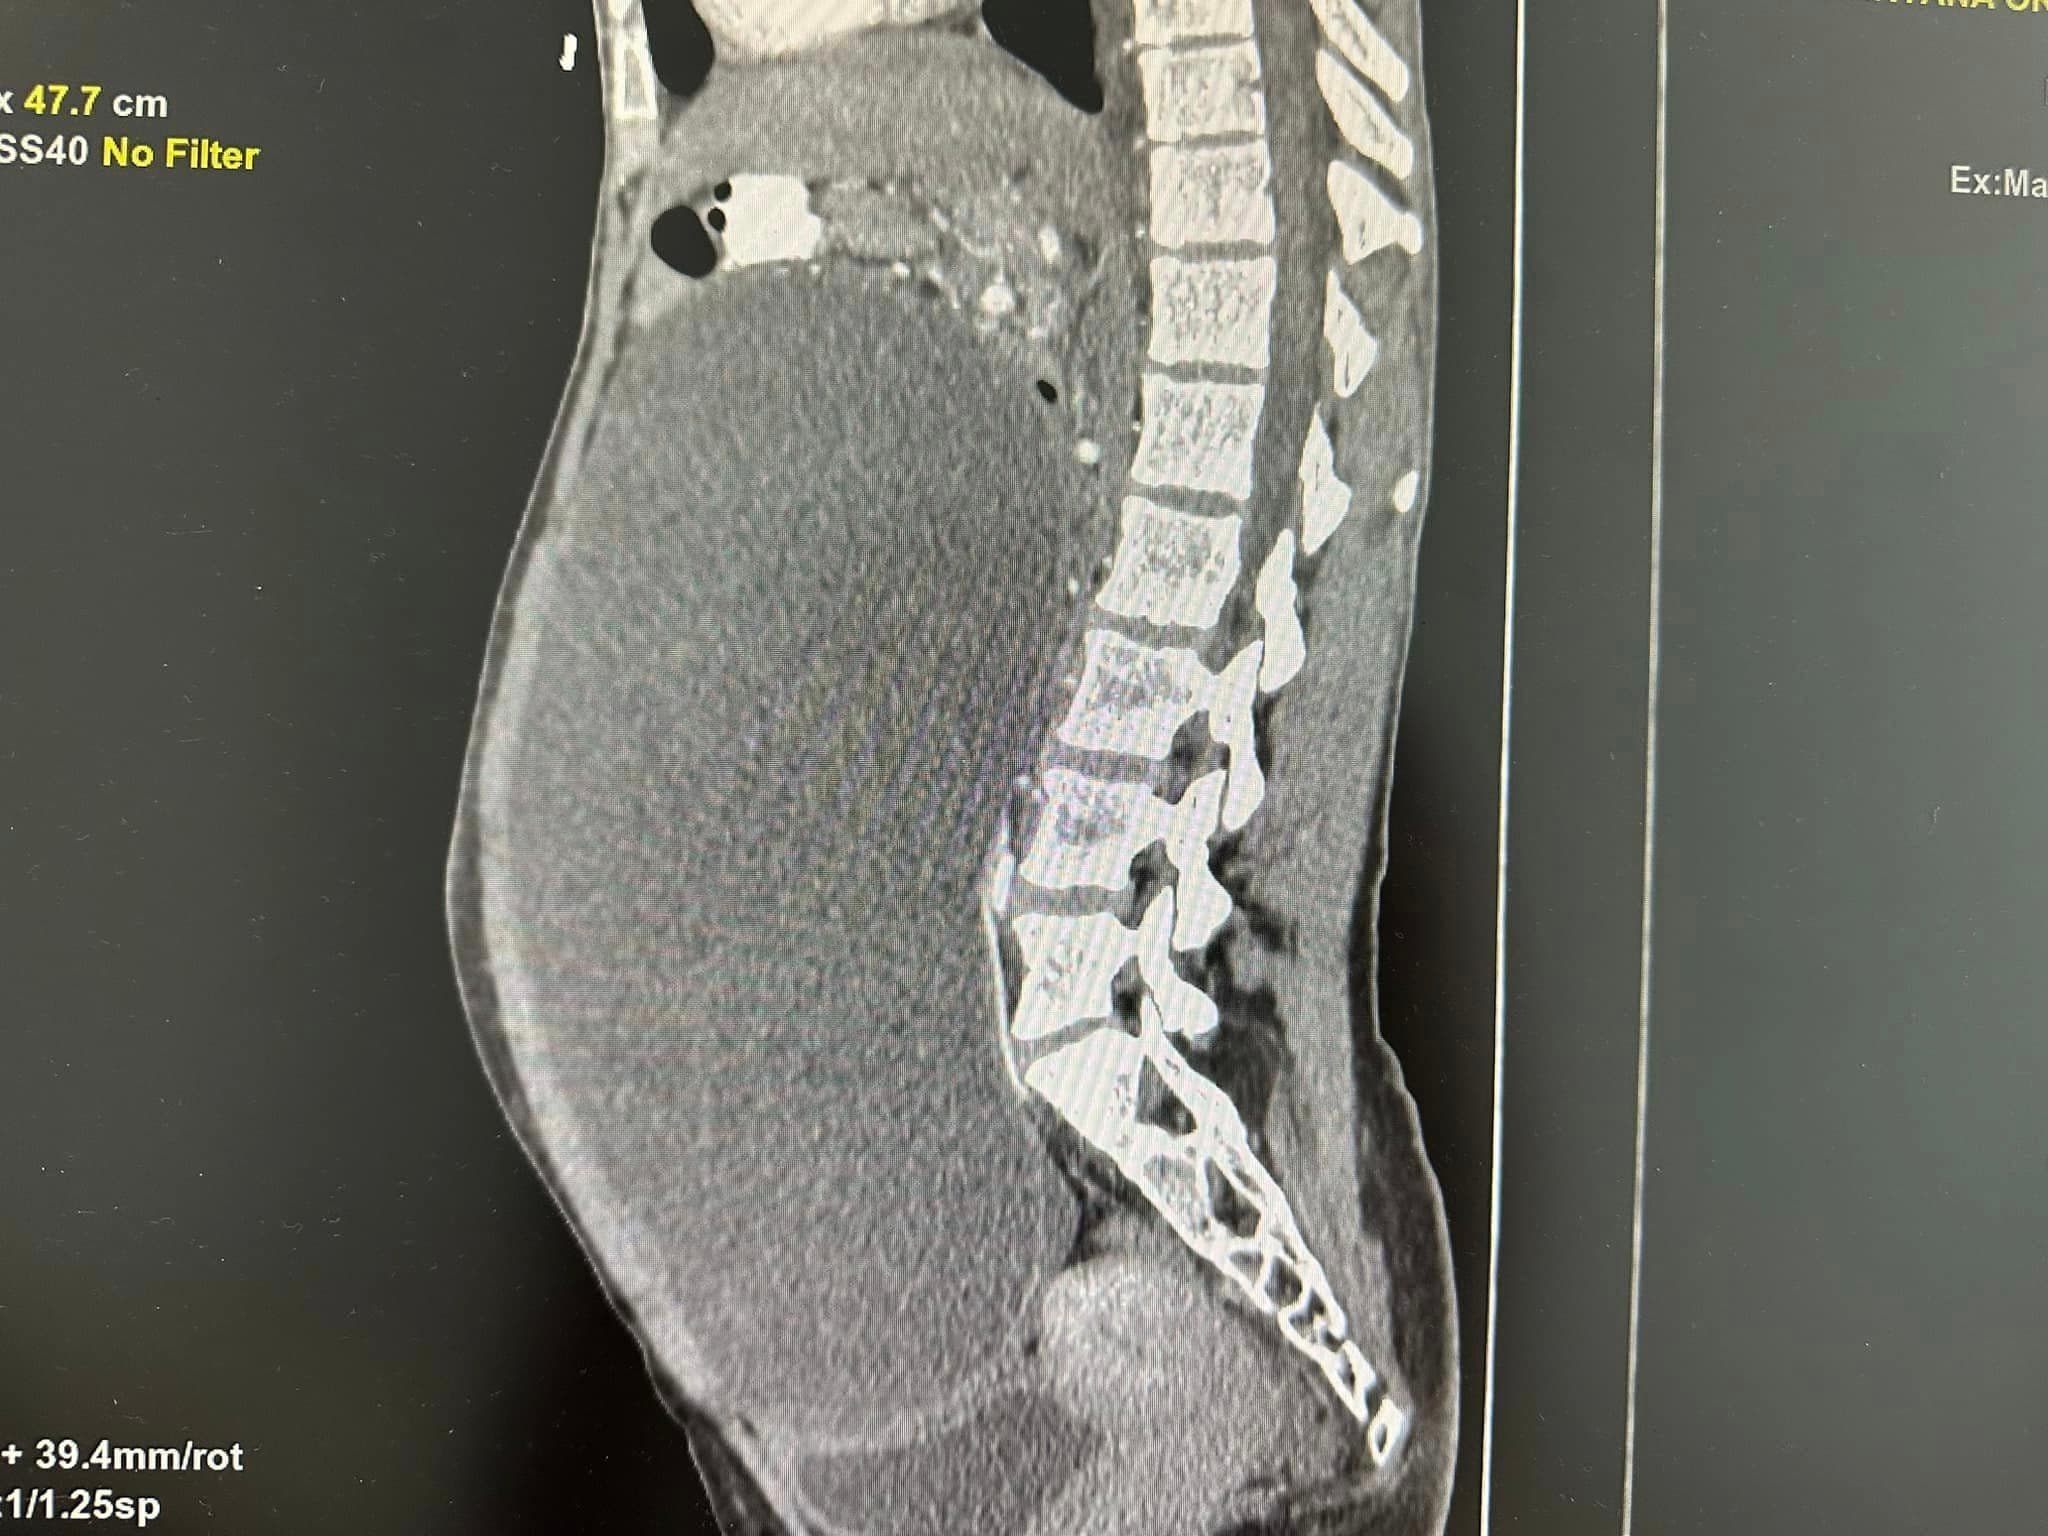

В лікарні зазначають, що протягом пів року молода жінка бачила як змінюється і росте її живіт. При цьому в інших частинах тіла вона зовсім не погладшала. На аномалію звернули увагу родичі і вмовили звернутися до лікаря. Жінка прийшла до спеціалістів та під час УЗД та КТ-обстеження медики виявили величезний новоутвір. Розміром – 20 на 25 см. Він займав уже всю черевну порожнину пацієнтки.

Лікарі видалили кістому через три розрізи по півтора сантиметри кожен. І забрали з неї ціле відро рідини – аж 9 літрів. А потому видалили і саму капсулу – лише вона важила 1,5 кг. Молоду жінку виписали додому вже на другу добу після операції.